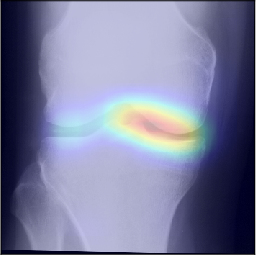

While machine learning-based approaches yield stronger prediction than conventional statistical models, (e.g. LR), they are less transparent, which can lead to lack of trust from clinicians. To address this drawback, various methods have been developed to explain the decisions of ”black-box systems” [24, 26, 27]. As such, we utilized the GradCAM approach [24] that allowed us generating an attention map, in order to highlight the zones where the CNN has paid its attention. While being attractive, this approach can also lead to wrong interpretations, i.e. there is no theoretical guarantee that the neural network identifies causal relationships between image features and the output variable. Therefore, a thorough analysis of the attention maps is required to assess the significance of certain features and anatomical zones picked-up by the model. Such analysis, however, could enable new possibilities for investigation of the visual features. For example, we observed interesting associations in the GradCAM-generated attention maps (Figure 5), some of which are not captured by KL grading. As such, tibial spines (previously associated with OA progression [28]) were highlighted in multiple attention maps. These associations, however, do not hold for all the progressors.

Figure 3: Examples of GradCAM-based attention maps for the knees progressed from no osteoarthritis to osteoarthritis. Fine-grained sub-types of progression are also specified. The presented images are of 140×140140140140\times 140 mm.

Refer to caption

(a) KL-2 to KL-3, slow

(b) KL-2 to KL-3, fast

(c) KL-3 to KL-4, slow

(d) KL-3 to TKR

(e) KL-2 to KL-3, fast